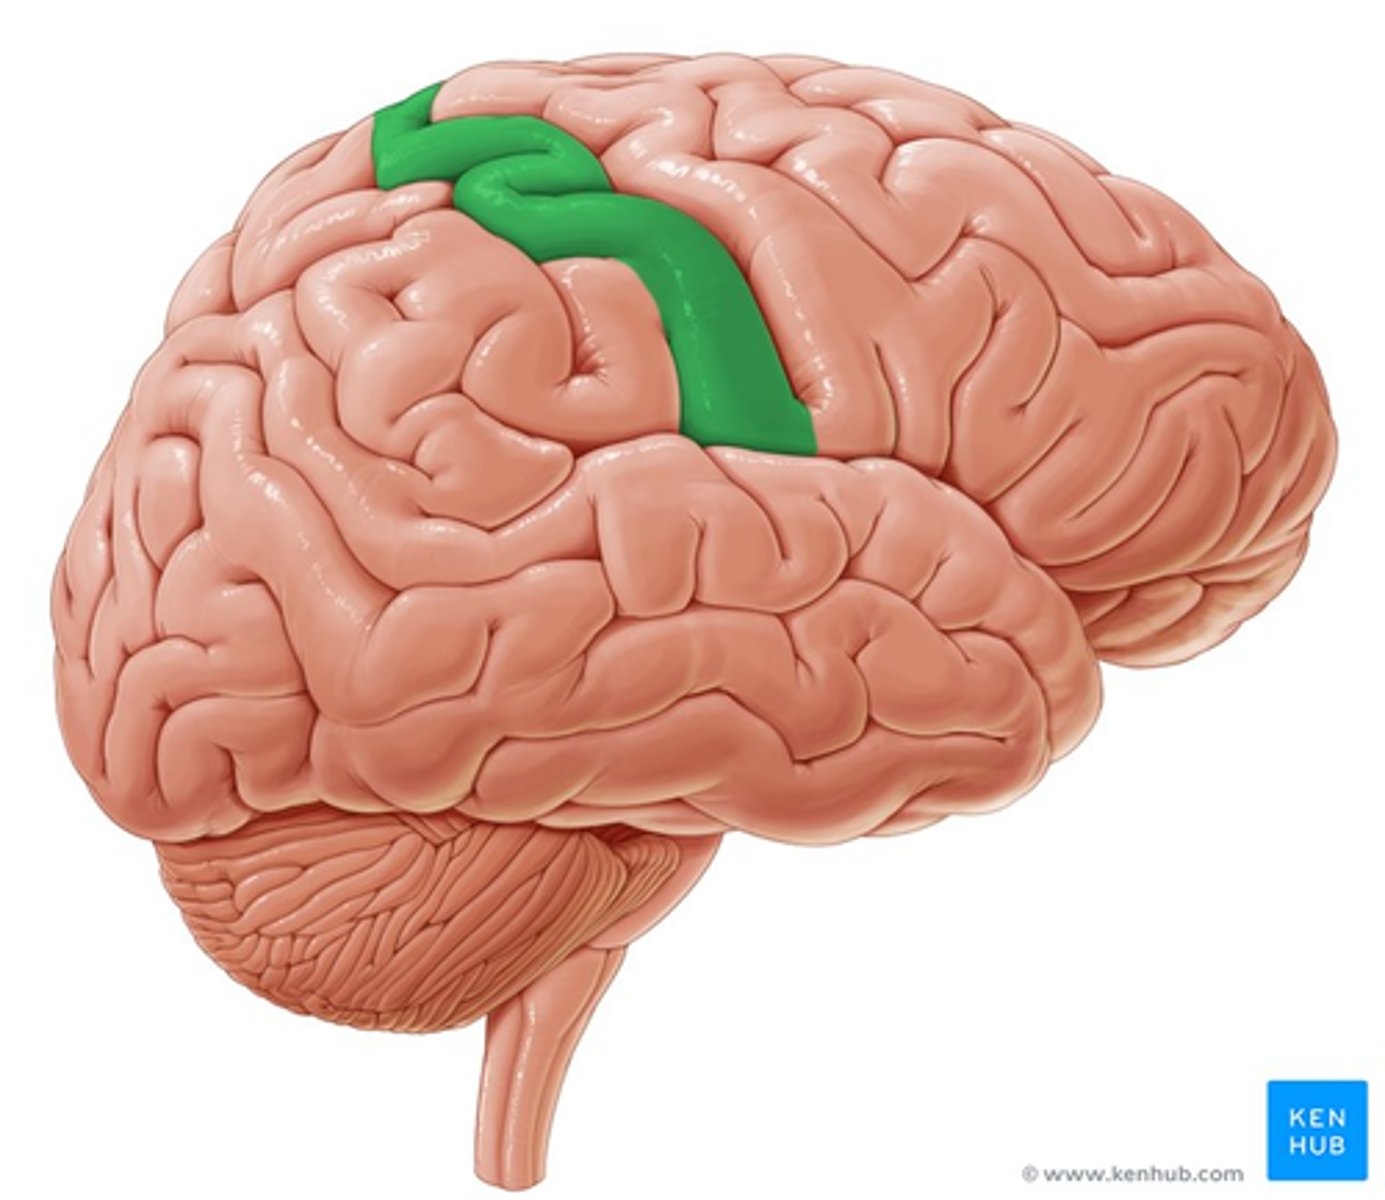

parietal lobe